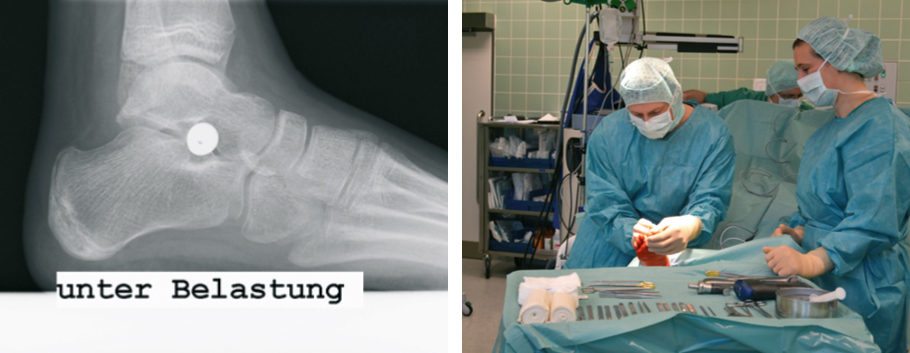

Hierzu steht seit einigen Jahren ein modernes minimal invasives Verfahren, die so genannte Arthrorise zur Verfügung. Über einen kleinen Schnitt von nicht mehr als 2 cm, wird eine hierfür entwickelte Spezialschraube in das untere Sprunggelenk eingebracht. Wesentliche Weichteile oder Gelenke werden hierbei weder versteift noch zerstört.

Durch die Schraube kommt es zur Aufrichtung des Plattfußes. Bereits nach zwei Wochen ist eine normale Belastung möglich. Die Schraube kann nach 2-3 Jahren wieder entfernt werden, die verbesserte Fußstellung bleibt dennoch bestehen.